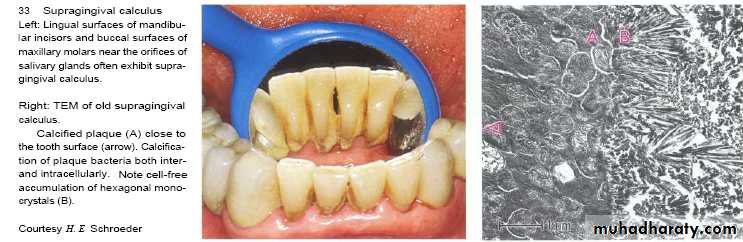

Supragingival calculus

It is yellow-white in colour ,located along gingival margins.

Large amount located at buccal aspect of upper 6 & lingual aspect of lower ant.teeth (next to stenson, warton & bartholin ducts).

Its easily detached, rapidly recur after removal .

Predominant flora in calculus are cocci, bacilli and filaments (especially in the outer layers), and occasionally spiral organisms.The bacteria near the enamel surface tend to have a reduced cytoplasm to cell wall ratio, suggesting that they are metabolically inactive.

Supragingival calculus contains more Gram-positive organisms, while subgingival calculus tends to contain more Gram negative species.

In some areas (especially the outer surface) cocci attach and

grow on the surface of filamentous microorganisms, giving a

'corn-cob' arrangement.

The filamentous bacteria tend to orient themselves at right angles to the enamel surface, producing a palisade effect (like books on a shelf).